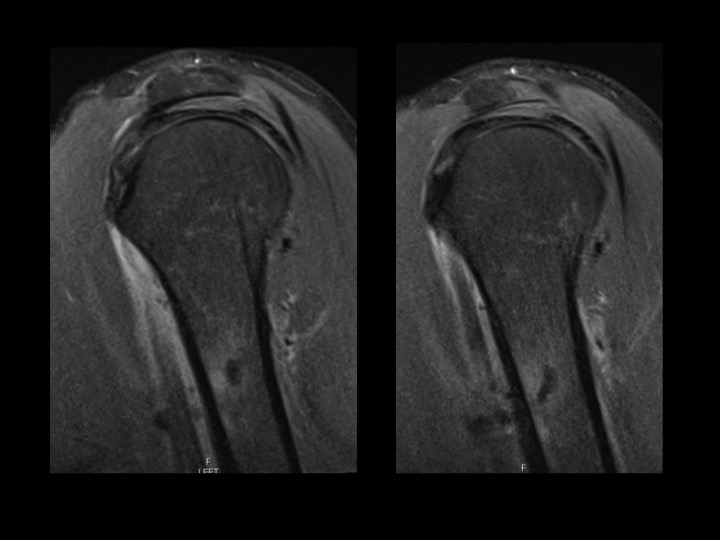

Fell 2 months earlier with minor persistent symptoms, acutely worse x 3 days opening a door. He reported night pain and pain with reaching. 80% improved after 2 days on Medrol dose pak. MRI shows subcortical humeral shaft marrow and parosteal edema with dark signal foci in the region of the pectoralis major insertion. CT shows both peri-tendinous calcifications as well has HADD deposits eroding through the cortex and into bone. Axillary XR clearly shows the peri-tendinous deposit; the cortical erosion is faintly visible....and I expect you can all see the intra-osseous calcific deposit.

tendon of pectoralis major ( RID2007 )